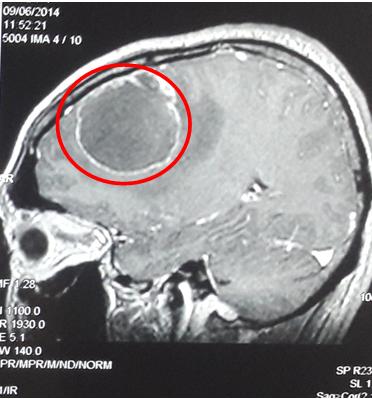

-       Chụp cộng hưởng từ sọ não: u não thùy trán đỉnh phải phải, kích thước 35 x 45mm, ngấm thuốc dạng viền, phù não xung quanh, nghĩ tới tổn thương thứ phát.

Hình 2: Hình ảnh chụp cộng hưởng từ sọ não trước điều trị (vòng tròn đỏ: u não thùy trán đỉnh phải, kích thước 35 x 45mm, ngấm thuốc dạng viền, phù não xung quanh)